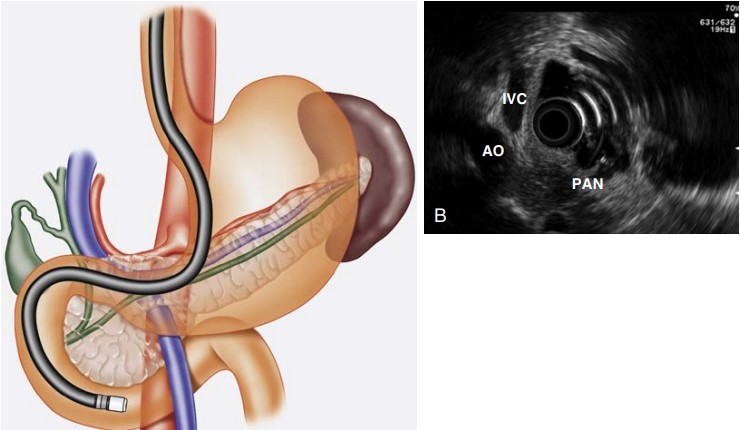

Examining Liver Abnormalities

The liver, a vital organ, can also be thoroughly examined using EUS. This includes:

- Identifying Liver Lesions: Pinpointing the nature of liver lesions, whether benign or malignant.

- Assessing Liver Cirrhosis and Portal Hypertension: EUS can help in staging liver cirrhosis and evaluating complications like varices.